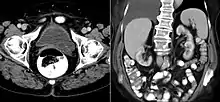

A ureterocele is a congenital abnormality found in the ureter. In this condition the distal ureter balloons at its opening into the bladder, forming a sac-like pouch. It is most often associated with a duplicated collection system, where two ureters drain their respective kidney instead of one. Simple ureterocele, where the condition involves only a single ureter, represents only twenty percent of cases.

- Cobra head sign is seen in radiography

IVU-shows Adder head appearance or Cobra head appearance. Cystoscopy-shows translucent cyst which is thin walled surrounding ureteric orifice